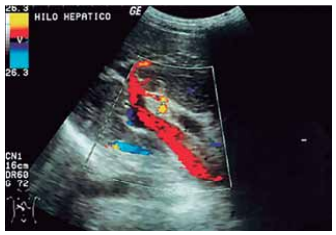

De acordo com Machado et al. na obra “Estudo doppler

na hipertensão portal” Radiol. Bras 2004 – “Atualmente, o

exame de ultrassonografia com doppler deve ser incluído

como avaliação inicial de qualquer suspeita de hipertensão portal. Os dados fornecidos por esse exame são de

extrema importância na condução clínica e cirúrgica dos

pacientes”.

O estudo a seguir permite a avaliação de estruturas vasculares e do fluxo de sangue dentro delas, especificamente, a

Doppler colorido demonstrando a veia porta (com fluxo hepatopetal), e a artéria hepática, anterior à veia porta.

(https://doi.org/10.1590/S0100-39842004000100009)